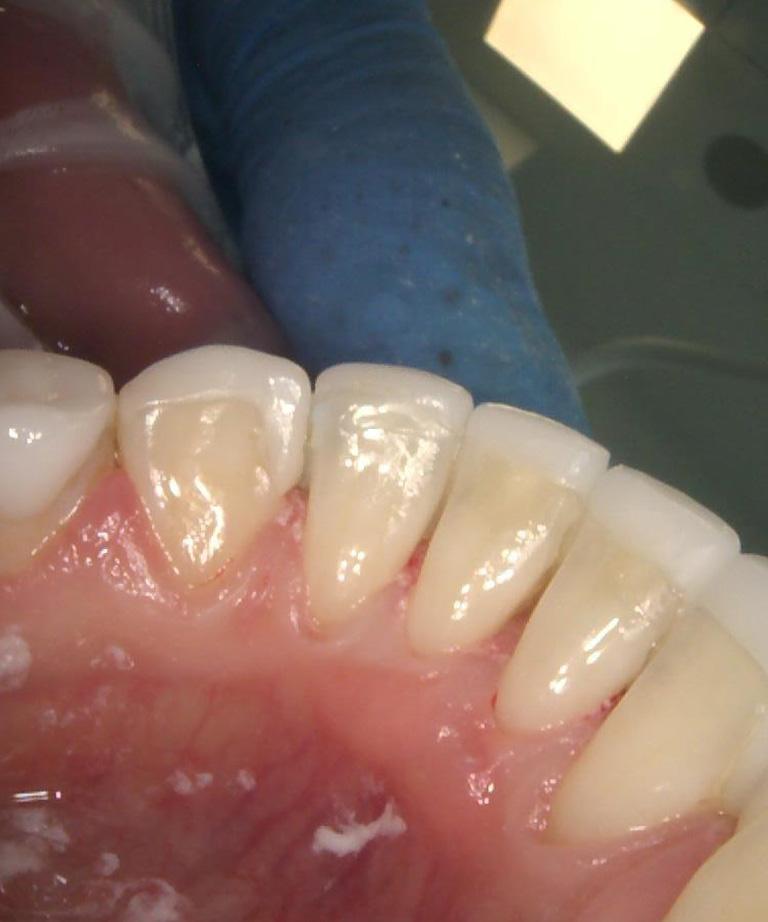

Dobrze przeprowadzony zabieg implantacji natychmiastowej daje efekty jak na pozostałych zdjęciach! Na każdym etapie leczenia mamy pełną kontrolę nad wszystkimi aspektami przyszłej odbudowy protetycznej – można powiedzieć, że zachowujemy to, co najtrudneijsze do odtworzenia, czyli kształt dziąseł.

Cytując Michała Mokijewskiego: „Pacjent przychodzi po idealny ząb, a nie po implant”.

Tylko implantacja natychmiastowa pozwala nam uzyskać taki efekt w zaledwie 3 wizyty.